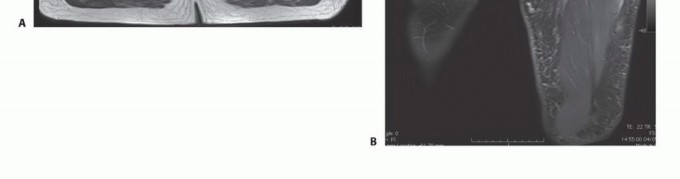

تُعد الأشعة المقطعية (CT) والتصوير بالرنين المغناطيسي (MRI) ضرورية لتحديد موقع ومدى الورم وعلاقته بعظم الفخذ والحزمة العصبية الوعائية.

التصوير بالرنين المغناطيسي (MRI): يُعتبر التصوير بالرنين المغناطيسي الأداة الأكثر قيمة لتقييم أورام الأنسجة الرخوة. يوفر صورًا مفصلة للأنسجة الرخوة، مما يساعد في تحديد حجم الورم وشكله وعلاقته بالعضلات والأوعية الدموية والأعصاب المحيطة. يمكن أن يوضح ما إذا كان الورم قد اخترق اللفافة أو امتد إلى حجرات أخرى. الأورام الكبيرة في العضلة الرباعية غالبًا ما تُزيح الأوعية الفخذية السطحية والعميقة. من المهم تحديد العلاقات التشريحية لهذه الأوعية بالورم قبل الاستئصال.